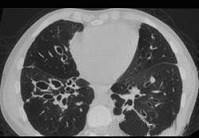

男,18岁,咳嗽,咳痰,咯血半月余,CT如图.选出最可能的诊断 ( )A.过敏性肺炎B.支气管扩张C.原发性肺结核D.大叶性肺炎E.肺癌

问题 男,18岁,咳嗽,咳痰,咯血半月余,CT如图.选出最可能的诊断 ( )

选项 A.过敏性肺炎 B.支气管扩张 C.原发性肺结核 D.大叶性肺炎 E.肺癌

答案 B